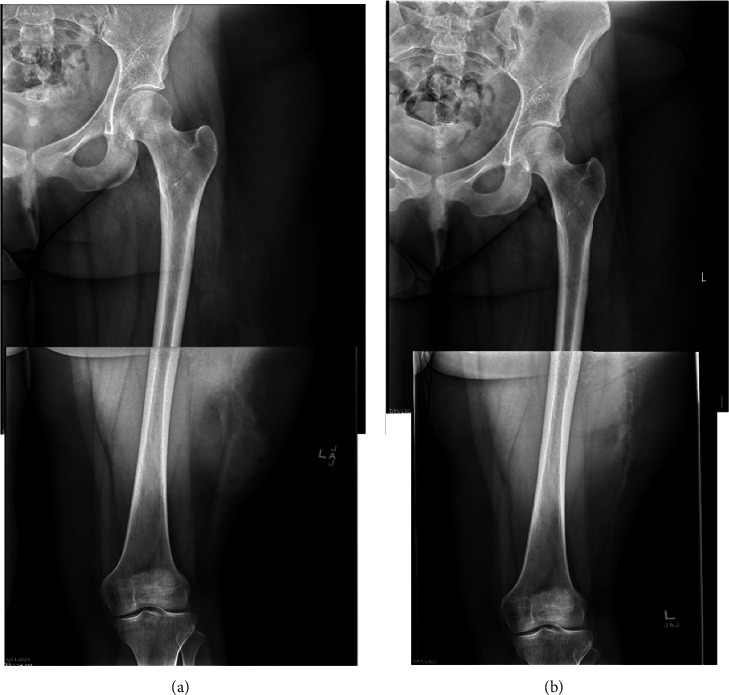

Morel-Lavallée lesions are serious internal degloving injuries associated with trauma. Its diagnosis and treatment can be challenging. We describe the surgical treatment of a case of a chronic Morel-Lavallée lesion in a pediatric patient who sustained an injury to her left thigh during an all-terrain vehicle accident more than a year ago.